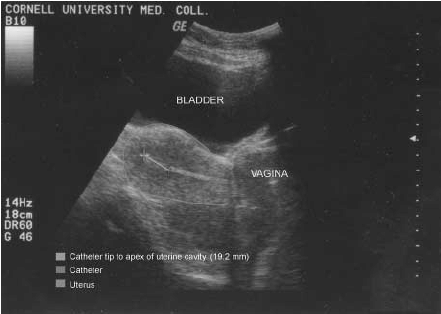

Simply put, an embryo transfer involves taking the fertilized egg and sperm and implanting the newly-formed embryo into an intended mother or surrogate's uterus. The embryos’ placement within the uterus must be precise, so your fertility doctor will guide this transfer by a pelvic ultrasound.

Because the ultrasound gives your reproductive doctor visibility into the perfect placement for the catheter, they can reduce the possibility of the catheter touching your cervix. If this does occur, fear not, you will only experience a mild cramping sensation.

The embryo transfer itself is very similar to a pap smear, and is a short procedure, often lasting between 15 and 30 minutes. Your reproductive doctor will insert a speculum into the woman’s vagina with ultrasound for accuracy during this procedure. Then, your doctor will pass a catheter through the cervix and into the womb. From there, the embryos are passed through the tube and into the womb.